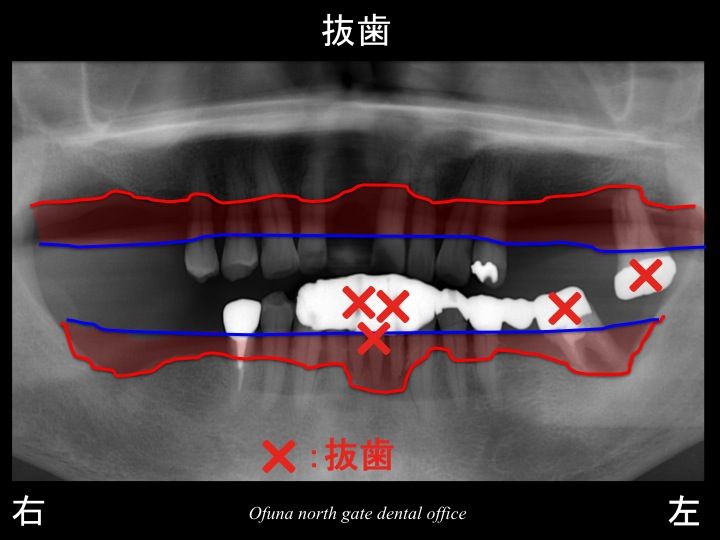

結論として、

上顎左側の奥歯の1歯と

下顎前歯部の3歯、

下顎左側の奥歯の1歯

は抜歯と判断しました。

まず、抜歯から始めなければいけません。

この理由として、歯周病治療を行っても感染原因を取除けない歯を放置しておくと、

取残しとなった歯周病細菌は必ず他の歯に感染します。

つまり 他の歯もダメになってしまいますのでどうしても 始めに抜歯が必要なのです。